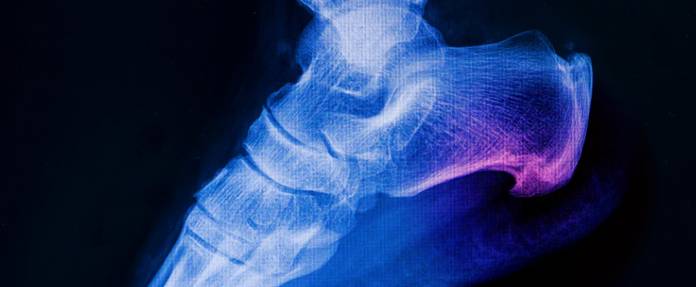

Röntgenbilder, Ultraschallaufnahmen oder MRT helfen, die richtige Vorgehensweise zu finden.